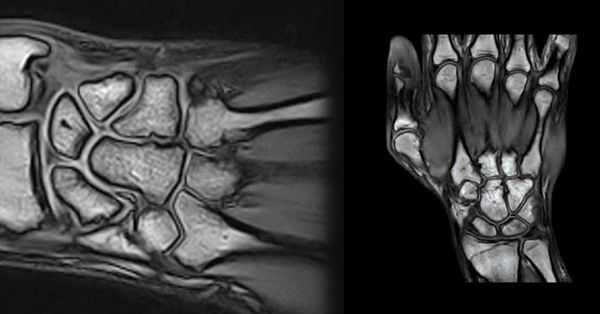

(Слева) Рентгенография в ЗП проекции: типичные признаки краевых эрозий при РА. Они визуализируются на раннем этапе эрозивного процесса в тех отделах кости, которые расположены внутри капсулы, но не имеют хрящевого покрытия. Эти отделы кости наиболее подвержены воспалительному процессу.

(Справа) Рентгенография в ЗП проекции: нормальная плотность костной ткани у пациента с ранней стадией РА. Единственным пораженным суставом является проксимальный межфаланговый сустав В, где визуализируются эрозии и значительное повреждение хряща. Примите во внимание, что на ранней стадии РА эрозивный процесс может поражать ПМФС с той же вероятностью, что и ПФС. (Слева) Рентгенография в ЗП проекции: узелок, который является причиной вдавленного дефекта подлежащей кости. Обратите внимание на уменьшение ширины хряща во 2-м ПФС по ходу краевой эрозии головки пястной кости. Характер и положение типичны для РА с ревматоидными узелками.

(Справа) Рентгенография в ЗП проекции: признаки выраженной, быстроразвивающейся лентовидной остеопении в дистальном отделе лучевой кости у мужчины 48 лет, а также отека мягких тканей и вероятной эрозия шиловидного отростка локтевой кости. (Слева) МРТ артрограмма, корональная плоскость, режим Т1: отек и эрозии шиловидного отростка локтевой кости и трехгранной кости В у того же пациента. Кроме того визуализируется разрыв ладьевидно-полулунной связки.

(Справа) МРТ, корональная плоскость, режим Т2 с подавлением сигнала от жира: подтверждается наличие эрозий шиловидного отростка локтевой кости и трехгранной кости у этого же пациента. Кроме того визуализирует еще одна эрозия ладьевидной кости В. Обратите внимание на умеренное истончение хряща в луче-ладьевидном суставе, в то время как остальной хрящ выглядит нормальным. Эрозии у данного пациента более выражены, чем можно было предположить по результатам рентгенографии.